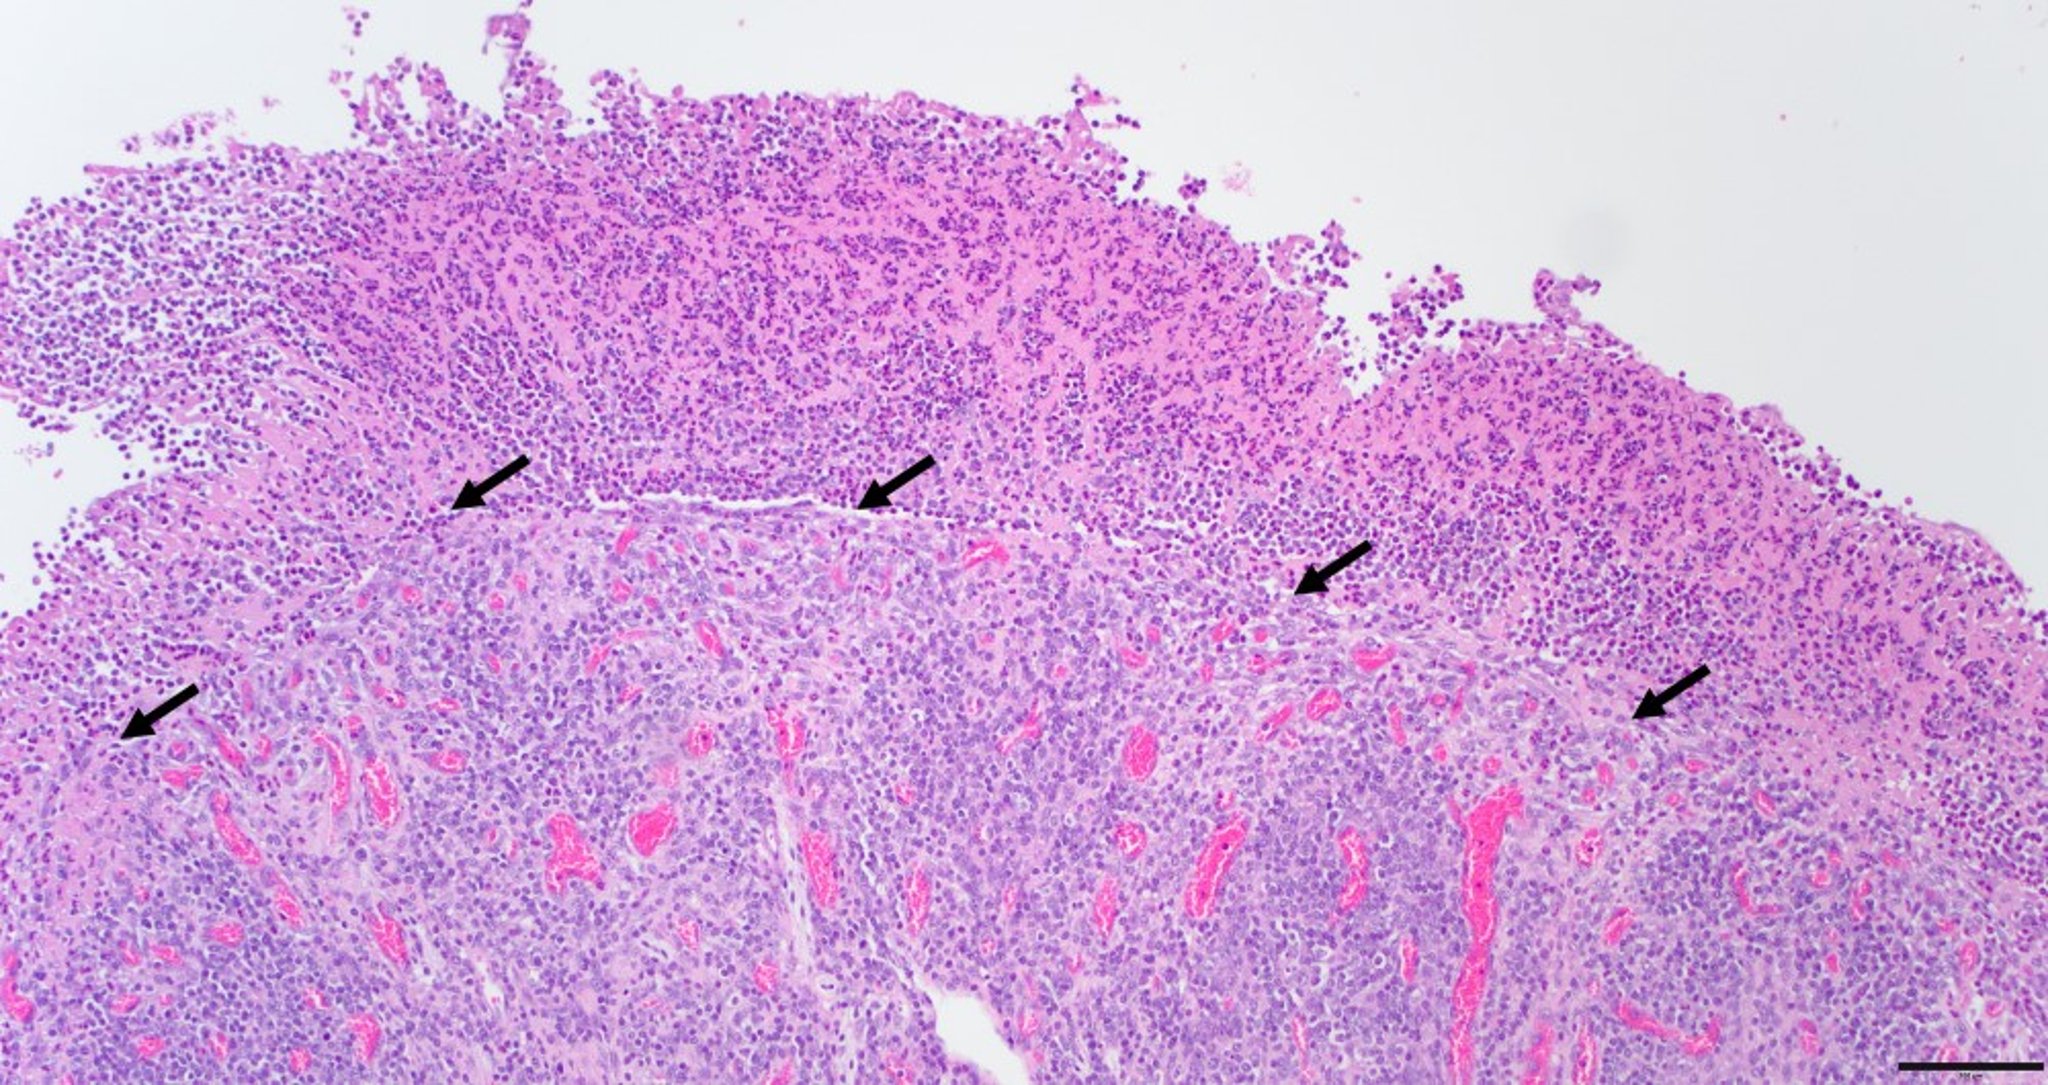

Enteritis por Salmonella, íleon, ternero

Microfotografía del íleon de un ternero de 3 semanas de edad con enteritis grave, aguda, ulcerativa y fibrinonecrótica debida a salmonelosis. La ulceración (pérdida completa de la mucosa) está cubierta por numerosos neutrófilos, fibrina y restos necróticos. Nótese la unión (indicada por flechas) entre la membrana fibrinonecrótica y la submucosa subyacente. La submucosa contiene vasos prominentes, células inflamatorias mononucleares mixtas y placas de Peyer. Barra de escala = 100 μm.

Cortesía de la Dra. Victoria Watson, Michigan State University Veterinary Diagnostic Laboratory.